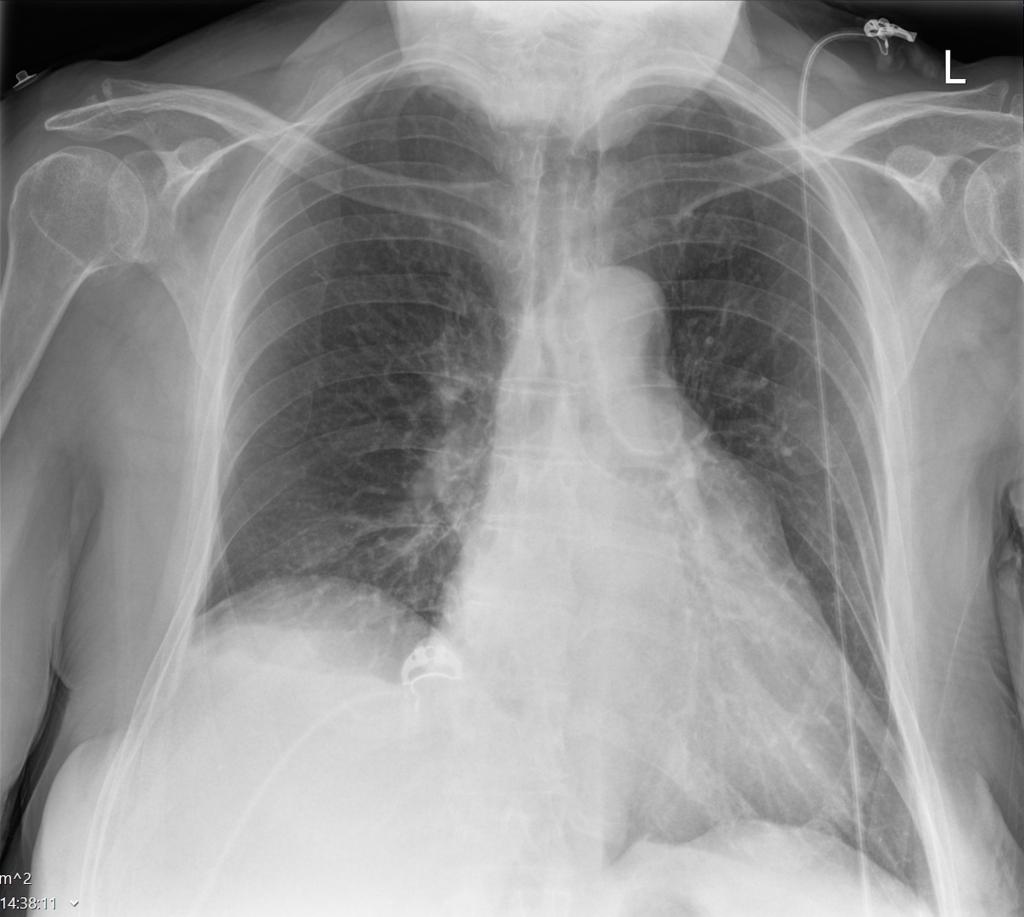

Een 74-jarige vrouw, bekend met astma en hartfalen, wordt verwezen naar de Eerste Harthulp vanwege progressieve dyspneu. Voorafgaand aan deze klacht had zij herpes zoster rechts op de thorax en in de nek ontwikkeld, ter plaatse van dermatoom C4-C5.